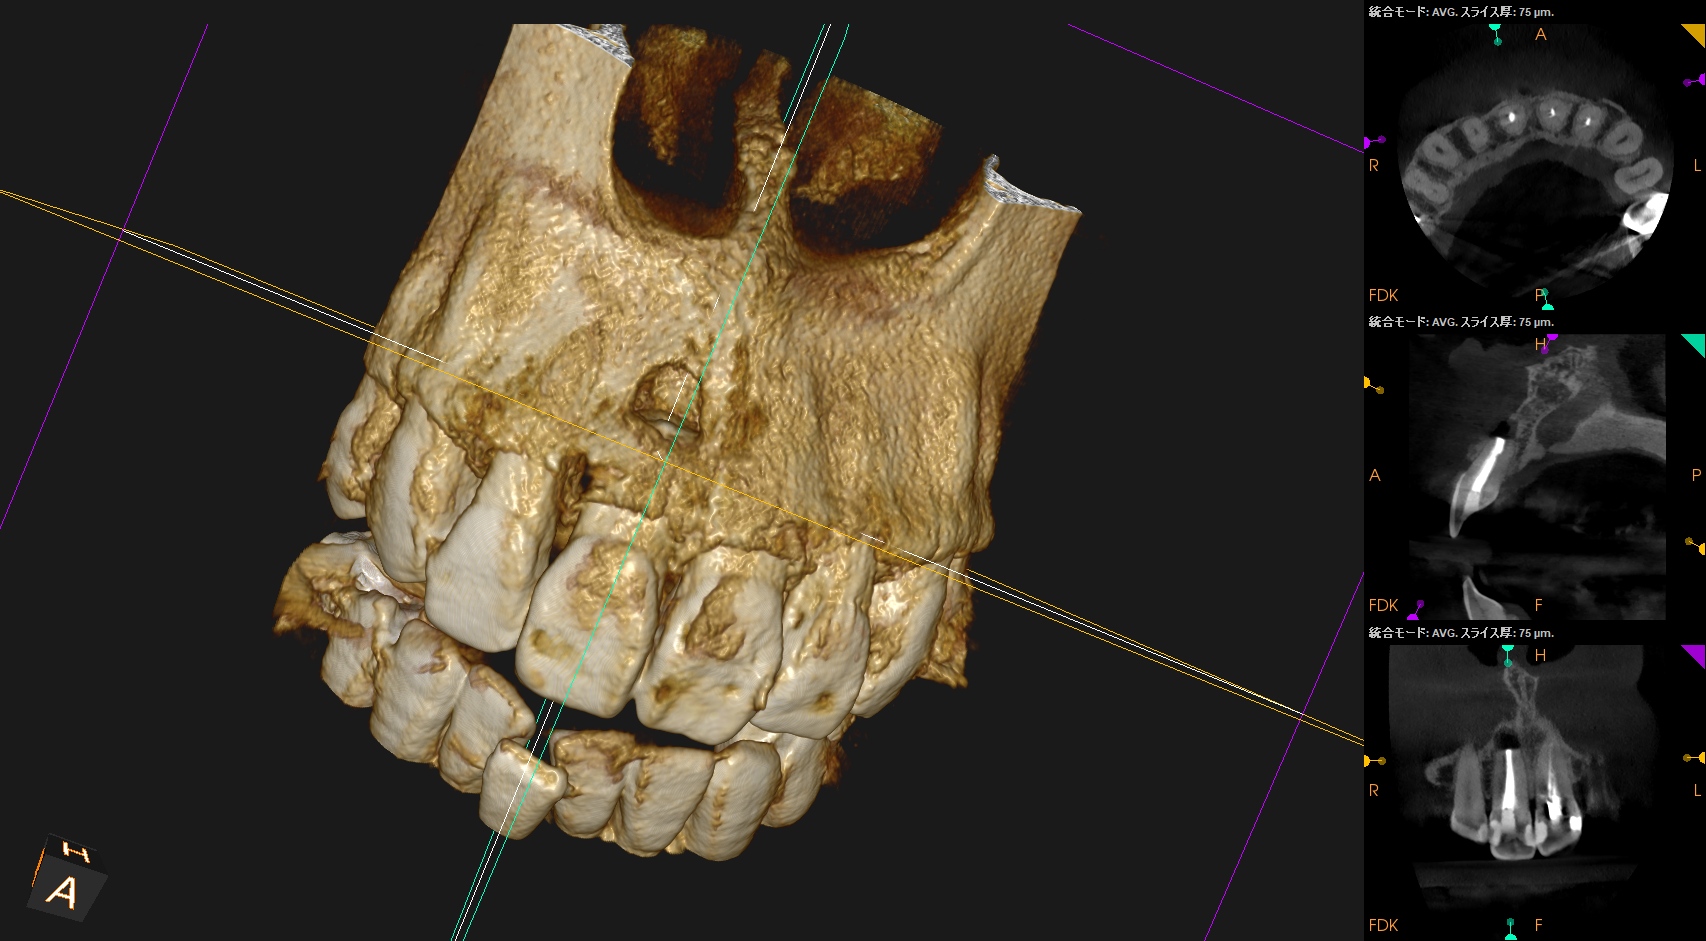

CBCT(2025.6.3)

#8はApexが歯槽骨からはみ出ている。

PA所見から考察するに、再治療よりも外科治療だろう。